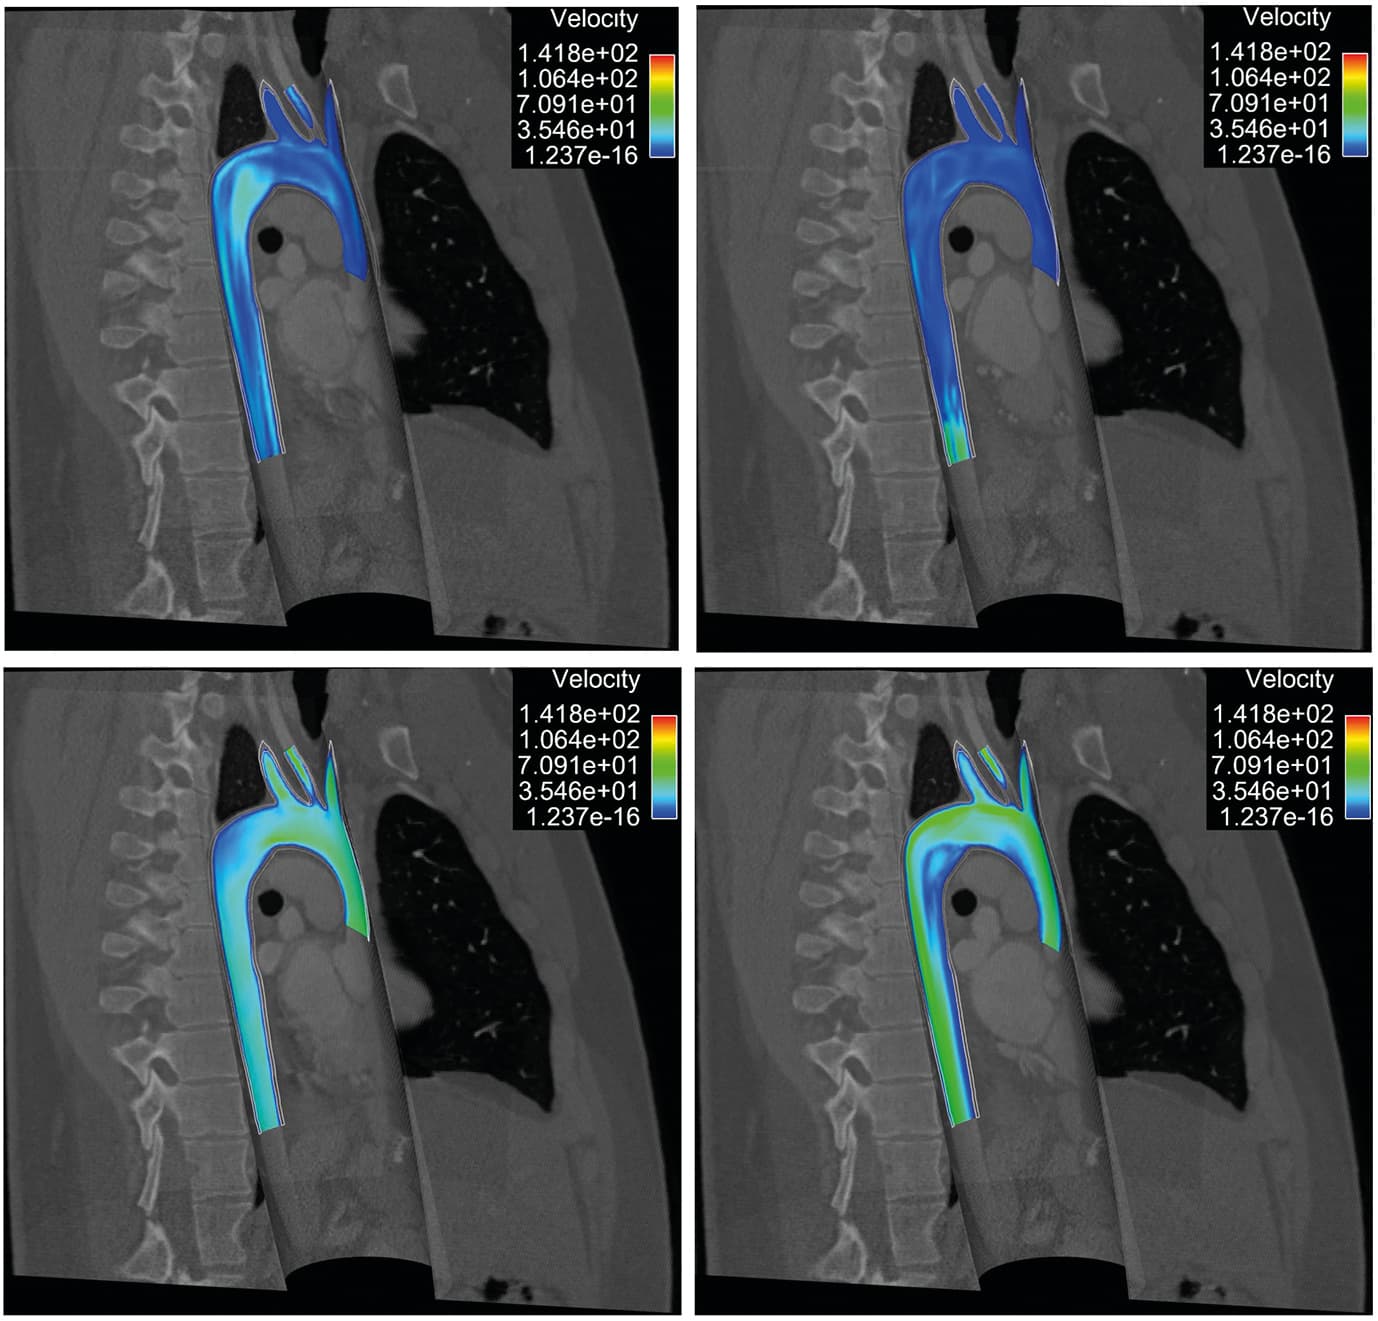

Filtering: From space conquest to cardiovascular modelling

and can be made rapidly decreasing provided that and remain moderate and is taken sufficiently large. This approach has been implemented with multiple refinements by Moireau et al. [39 P. Moireau, D. Chapelle and P. Le Tallec, Filtering for distributed mechanical systems using position measurements: perspectives in medical imaging. Inverse Problems25, 035010, 25 (2009) ], comparing in-depth the displacement vs. velocity controls.